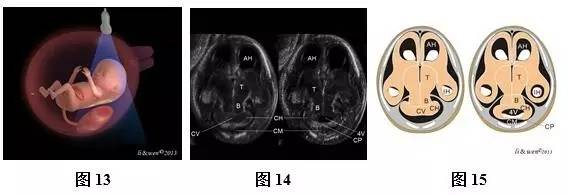

超声扫查方法:声束平面从胎儿前额进入,通过胎儿侧脑室对胎儿颅脑进行横切面扫查(图10),即可获得侧脑室水平横切面(图11,12);然后声束平面以前额为基点,向胎儿尾侧和前方扫查(图13,16,19,22),依次可获得小脑水平横切面(图14,15)、双眼球冠状切面(图17,18)、鼻后三角冠状切面(图20,21)和鼻唇冠状切面(图23,24)。

标准切面判断标准:(1)侧脑室水平横切面:可观察到强回声的脑中线把两侧大脑半球分开,两侧大脑半球内主要为侧脑室及其内的脉络丛占据,大脑实质仅表现为侧脑室周围薄层低回声带,强回声脉络丛几乎充满两侧侧脑室。(2)小脑横切面:可观察到脑中线、丘脑、小脑、第四脑室及颅后窝池等。(3)双眼球冠状切面:可观察到双眼球、硬腭、下颌骨、双耳等。(4)鼻后三角冠状切面:可观察到两块鼻骨、上颌骨、上牙槽及下颌骨等结构。(5)鼻唇冠状切面:可观察到上唇、下唇及鼻等结构。

注:BM为脑中线;CP为脉络丛;T为丘脑;CB为小脑;CM为颅后窝池;EYES为眼球;EAR为耳;NB为鼻骨;SM为上颌骨;IM为下颌骨;ST为上牙槽;N为鼻;UL为上唇;LL为下唇;CH,小脑半球;CV,小脑蚓部;CP,脉络丛;FV,第4脑室;B,脑干

图10~24胎儿颅脑及颜面扫查方法及超声声像图和模式图。图10侧脑室横切面扫查模式图;图11、12侧脑室横切面声像图及模式图;图13小脑横切面扫查模式图;图14、15小脑横切面声像图及模式图;图16双眼球冠状切面扫查模式图;图17、18双眼球冠状切面声像图及模式图;图19鼻后三角冠状切面扫查模式图;图20、21鼻后三角冠状切面声像图及模式图;图22鼻唇冠状切面扫查模式图;图23、24鼻唇冠状切面声像图

主要观察的解剖结构及内容:侧脑室横切面主要观察脑中线是否存在,左右大脑半球是否对称等。小脑横切面主要观察脑中线是否存在,颅后窝池是否存在等。双眼球冠状切面主要观察双侧眼球是否存在、大小及位置,双耳是否存在,硬腭是否连续完整等。鼻后三角冠状切面主要观察鼻骨是否存在,上牙槽是否连续完整等。鼻唇冠状切面主要观察上唇是否连续完整、鼻的形态等。